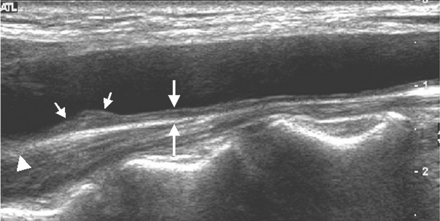

We assessed the presence of plaques in the CCA, bifurcation, and ICA, and defined plaques as focal widening of the vessel wall of more than 50% relative to adjacent segments, with protrusion into the lumen, composed of calcified or noncalcified components. Protrusion was visually determined. The total plaque score reflected the total number of sites with plaques and ranged from 0 to 6 (each of the CCAs, bifurcations, and ICAs, bilaterally). To access CCA-IMT, we focused on far-wall IMT, because far-wall measurements are considered more valid than near-wall measurements. IMT of the far wall was defined as the distance between the leading edge of the lumen-intima interface and the leading edge of the media-adventitia interface (Fig 1).

Longitudinal scan of carotid ultrasonogram. Measurement of CCA-IMT (large arrows) at the far wall of the common carotid artery is shown. The carotid plaque (small arrows) in the distal common carotid artery is seen. The arrowhead represents carotid bifurcation.

Far-wall IMT of both CCAs was measured at 3 sites (thickest point, and at sites 1 cm upstream and downstream, free from plaque) using Digimatic calipers (Mitutoyo, Kawasaki, Japan) on the longitudinal views. The maximum and mean IMT of the carotid arteries were assessed. The mean CCA-IMT was defined as the mean IMT of the right and left CCAs, calculated from 3 measurements on each side. The maximum CCA-IMT (max CCA-IMT) was defined as the average of the thickest wall of the right and left CCAs. If there was uniform intimal thickening in the CCA, we measured intimal thickness every 1 cm from the bifurcation to the end of the CCA. Then, we made 3 measurements: at the thickest point and 1 cm upstream and downstream.